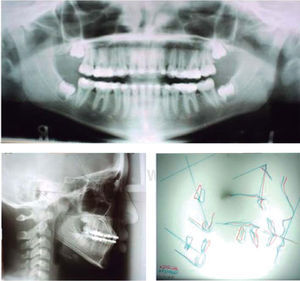

The panoramic radiograph showed the presence of the upper and lower left third molar germs, apparently healthy bony ridge levels, appropriate root height, and retained upper canines. The lateral headfi lm was traced with the McLaughlin cephalometry and showed results within the standard values. A Witts appraisal of 9mm describes the patient's diagnosis as a pseudo class III. It was inferred that the Witts was increased due to the forward mandibular entrapment because of the maxillary hypoplasia and increased overbite which were caused by the premature replacement of the deciduous teeth.

Her skeletal dental and soft tissues features allowed the malocclusion to be classifi ed as a pseudo class III (Table I).

Initial cephalometric values with McLaughlin analysis.

| Plane | Norm | PX |

|---|---|---|

| SNA | 82° | 81° |

| SNB | 80° | 82° |

| ANB | 2° | 1° |

| Witts | -1 mm | -9 mm |

| Go-Gn: SN | 32° | 31° |

| FM | 26° | 25° |

| MM | 28° | 27° |

| L: A-Pg | 6 mm | 7 mm |

| T: A-Pg | 2 mm | 2 mm |

| L: Max PI | 110° | 107° |

| T: Mad PI | 95° | 90° |

| A-Na Perp | 3mm | -2 mm |

| Pg-Na Perp | -4 mm | -4 mm |

| Palat-Occ PI | 10° | 11° |

| Mp-Occ PI | 12° | 11° |

| U1-Occ PI | 55° | 62° |

| L1-Occ PI | 72° | 75° |